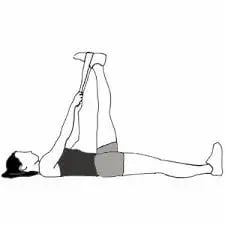

La tecnología se complementa con terapia manual específica del pie y el tobillo y con un programa de ejercicio terapéutico progresivo.

El ejercicio es clave para mejorar la tolerancia a la carga, recuperar la función del pie y reducir el riesgo de recaídas, trabajando tanto la musculatura del pie como el complejo gemelo-sóleo.